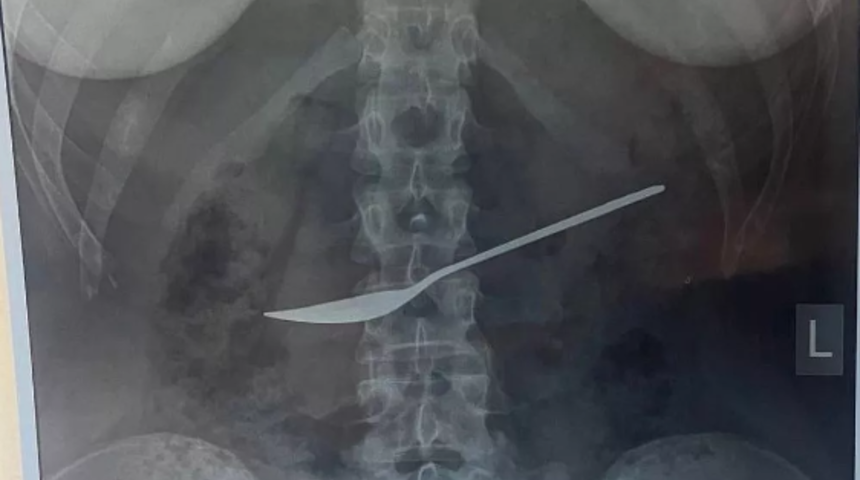

MYNET|DIŞ HABERLER Rusya'da ismi açıklanmayan bir kadın hasta geçmeyen karın ağrısı şikayetiyle doktora başvurdu. Rusya'daki Vologda Devlet Bölge Klinik Hastanesi'nde hastaya tıbbi müdahale yapıldı ve personel, ağrısının nedenini bulmaya çalışmak için bir dizi röntgen çekti.

Röntgen sonuçlarında hastanın midesine saplanan 20 cm uzunluğunda bir metal kaşık tespit edildi. Vakanın kendileri için de şaşkınlık verici olduğunu dile getiren Doktor Dmitry Vankov, "Kıza hemen özofagogastroduodenoskopi uygulandı. Video endoskop kullanılarak mide muayenesi yapıldı ve bu, doktorların tanıyı doğrulamasına yardımcı oldu. Kaşık özel bir halka ile yakalandı ve yemek borusu yoluyla mideden çıkarıldı" ifadelerini kullandı.

Vankov ayrıca, kızın sağlık durumunun iyi olması ve işlemin ardından derhal eve taburcu edilmesi nedeniyle ek ameliyat ve hastaneye kaldırılmanın gereksiz olduğunu da belirtti.